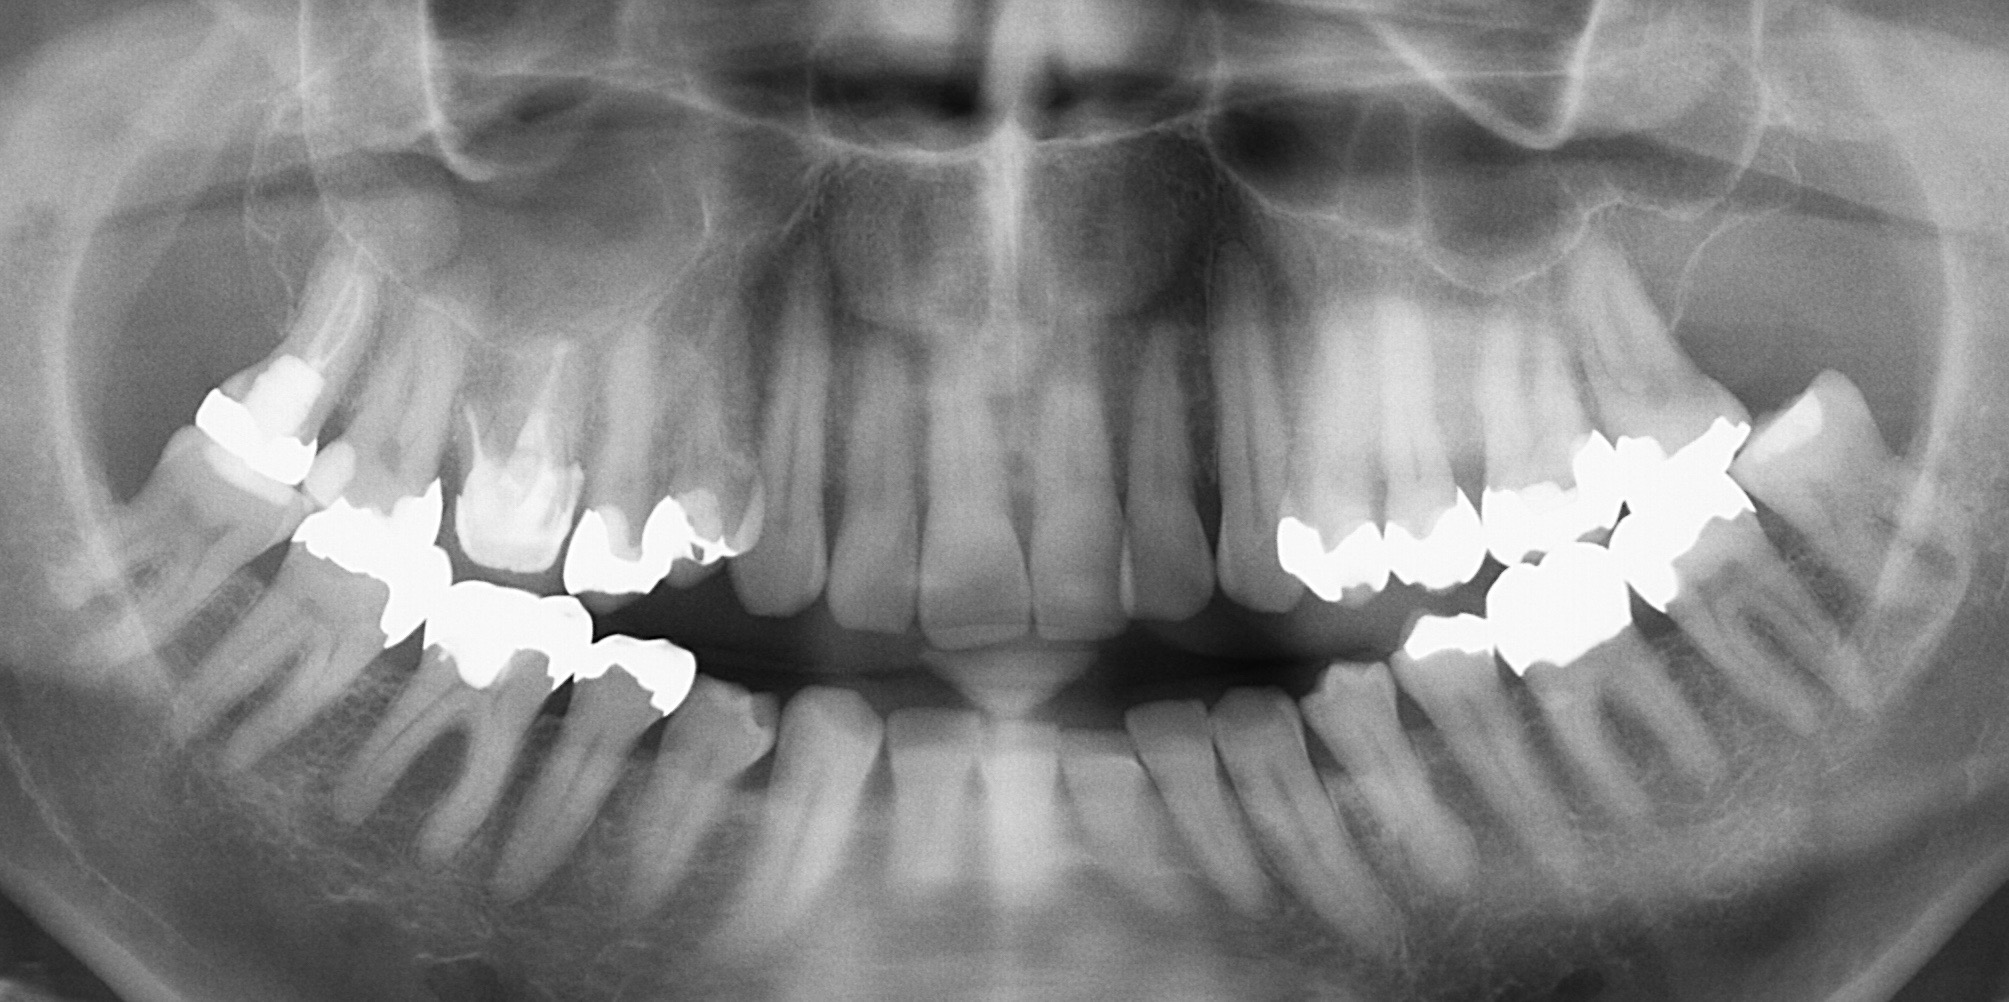

Saving hopeless teeth – Teil 28/5